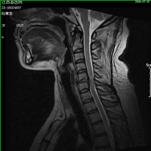

颈椎间盘突出、颈椎管狭窄——开展颈椎前路、后路手术治疗颈椎间盘突出、颈椎管狭窄,解除许多患者病痛,通过网上会诊方便患者,在家就能得到著名脊柱外科专家王少波教授诊治。

1).C4/5、C5/6间盘突出术前、 术后(C5椎体次全切除,钛笼植入)

2). C5-C6间盘突出术前、 术后(间盘切除,Cage植入)